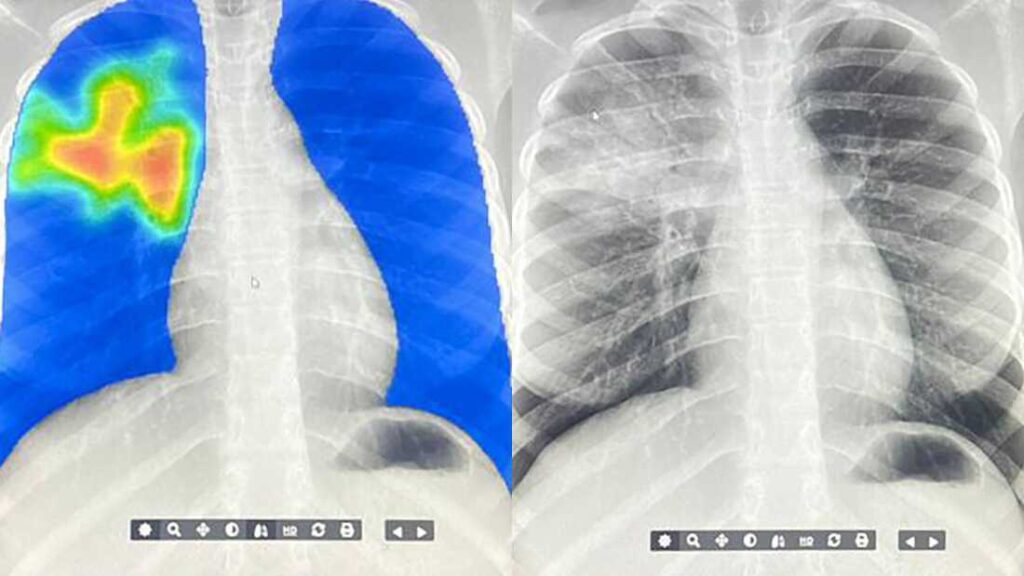

Many low- and middle-income countries are using AI to screen for tuberculosis. This AI model produces what looks like a heat map with spots highlighted in yellow-red that indicate the algorithm detects signs of TB. ARCAD Santé PLUS

At the Boniaba Community Health Center, the mother is one of dozens of people who get an x-ray from a mobile x-ray machine that Diakité Lancine has set up. He’s not a doctor but has been trained to take x-rays. The image he snaps is sent directly to his computer, where the AI model reads it and spits out a score based on how much AI thinks the image looks like TB and a picture of the person’s lungs that looks almost like a heat map.

“The blue there is nothing bad, but whenever you see the red — the red means this part is not good,” explains Lancine on the morning he screens the mother.

As soon as the mother’s screening comes back with several red patches, he collects a sputum sample to send to the lab for confirmation. Then he tells her to go home quickly and bring her five kids back so he can check them too. TB spreads through the air when someone with active TB coughs, laughs or talks and can be transmitted readily in households.